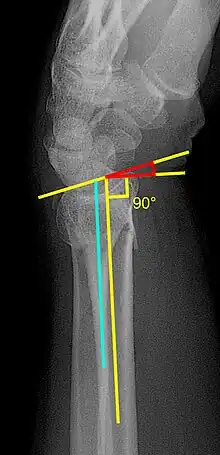

- Volar or dorsal tilt - A line is drawn joining the most distal ends of the volar and dorsal side of the radius. Another line perpendicular to the longitudinal axis of the radius is drawn. The angle between the two lines is the angle of volar or dorsal tilt of the wrist. Measurement of volar or dorsal tilt should be made in true lateral view of the wrist because pronation of the forearm reduces the volar tilt and supination increases it. When dorsal tilt is more than 11 degrees, it is associated with loss of grip strength and loss of wrist flexion.[5]

- Radial inclination - It is the angle between a line drawn from the radial styloid to the medial end of the articular surface of the radius and a line drawn perpendicular to the long axis of the radius. Loss of radial inclination is associated with loss of grip strength.[5]

- Radial length - It is the vertical distance in millimetres between a line tangential to the articular surface of the ulna and a tangential line drawn at the most distal point of radius (radial styloid). Shortening of radial length more than 4mm is associated with wrist pain.[5]

- Ulnar variance - It is the vertical distance between a horizontal line parallel to the articular surface of the radius and another horizontal line drawn parallel to the articular surface of the ulnar head. Positive ulnar variance (ulna appears longer than radius) disturbs the integrity of triangular fibrocartilage complex and is associated with loss of grip strength and wrist pain.[5]